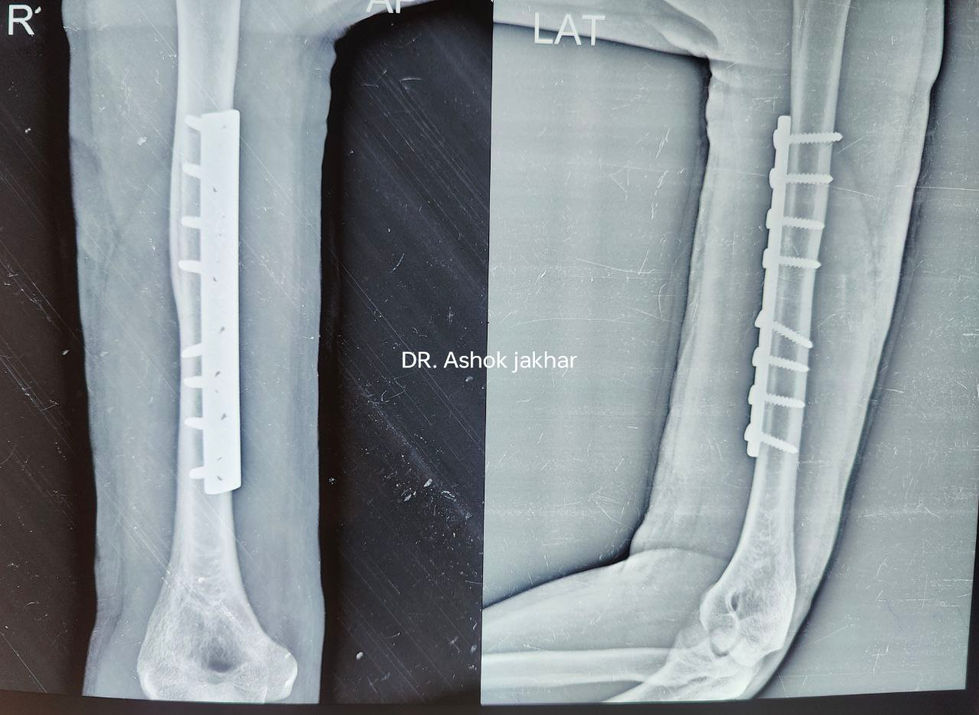

Orthopedic Surgery Showcase

A collection of X-ray images and surgical procedures showcasing orthopedic surgery, including the installation of surgical screws, plates, and performing surgery under bright operating room lights.